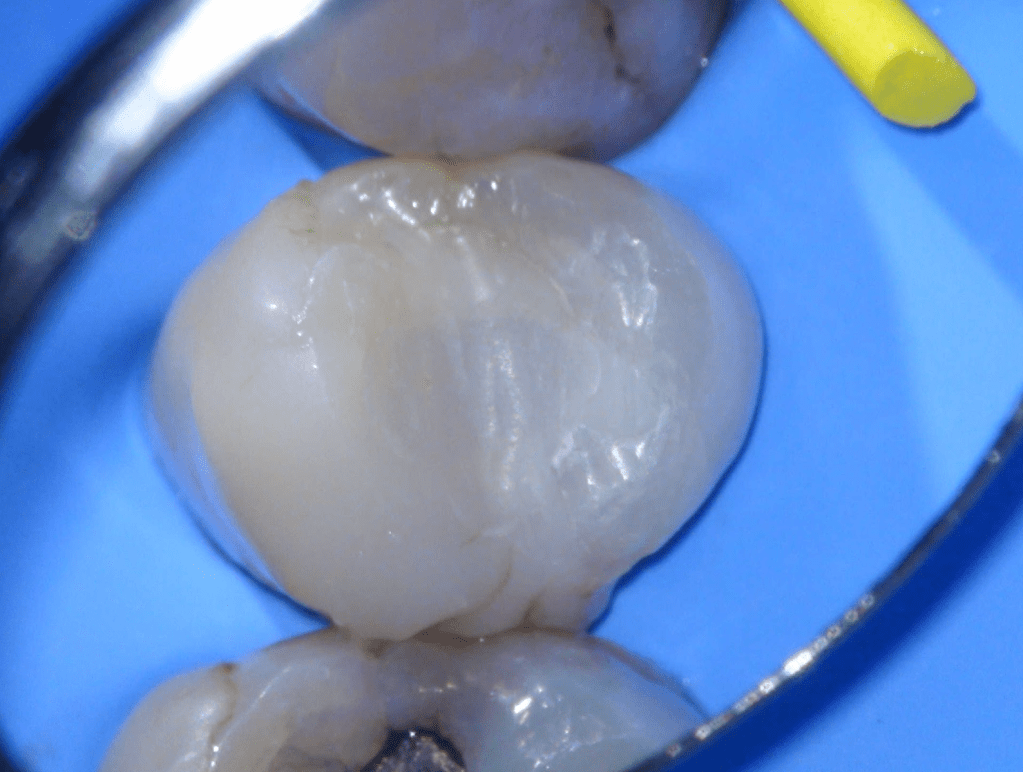

Diagnóstico de fisuras y fracturas

Diente fisurado regeneración total

Diente fisurado tratable

Diente fisurado tratable con endodoncia

Diente fisurado tratable endodoncia 2

Fisura, remoción amalgama para explorar

Fractura cuspídea tratable